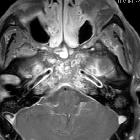

Osteomyelitis im Clivus